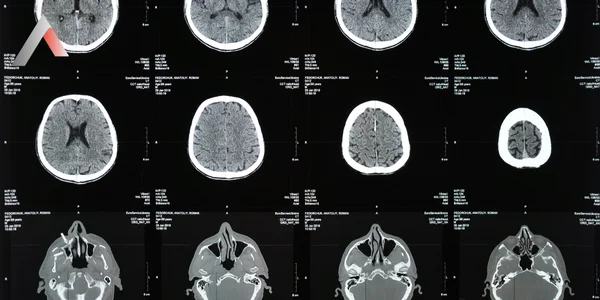

Başlıca teşhis yöntemleri:

• BT Tarama (Bilgisayarlı Tomografi): Özellikle kafa tabanı kırıklarının tespitinde kullanılır.

• MR Görüntüleme: Omurga ve beyin zarını ayrıntılı incelemek için kontrastlı MR çekimi yapılabilir.